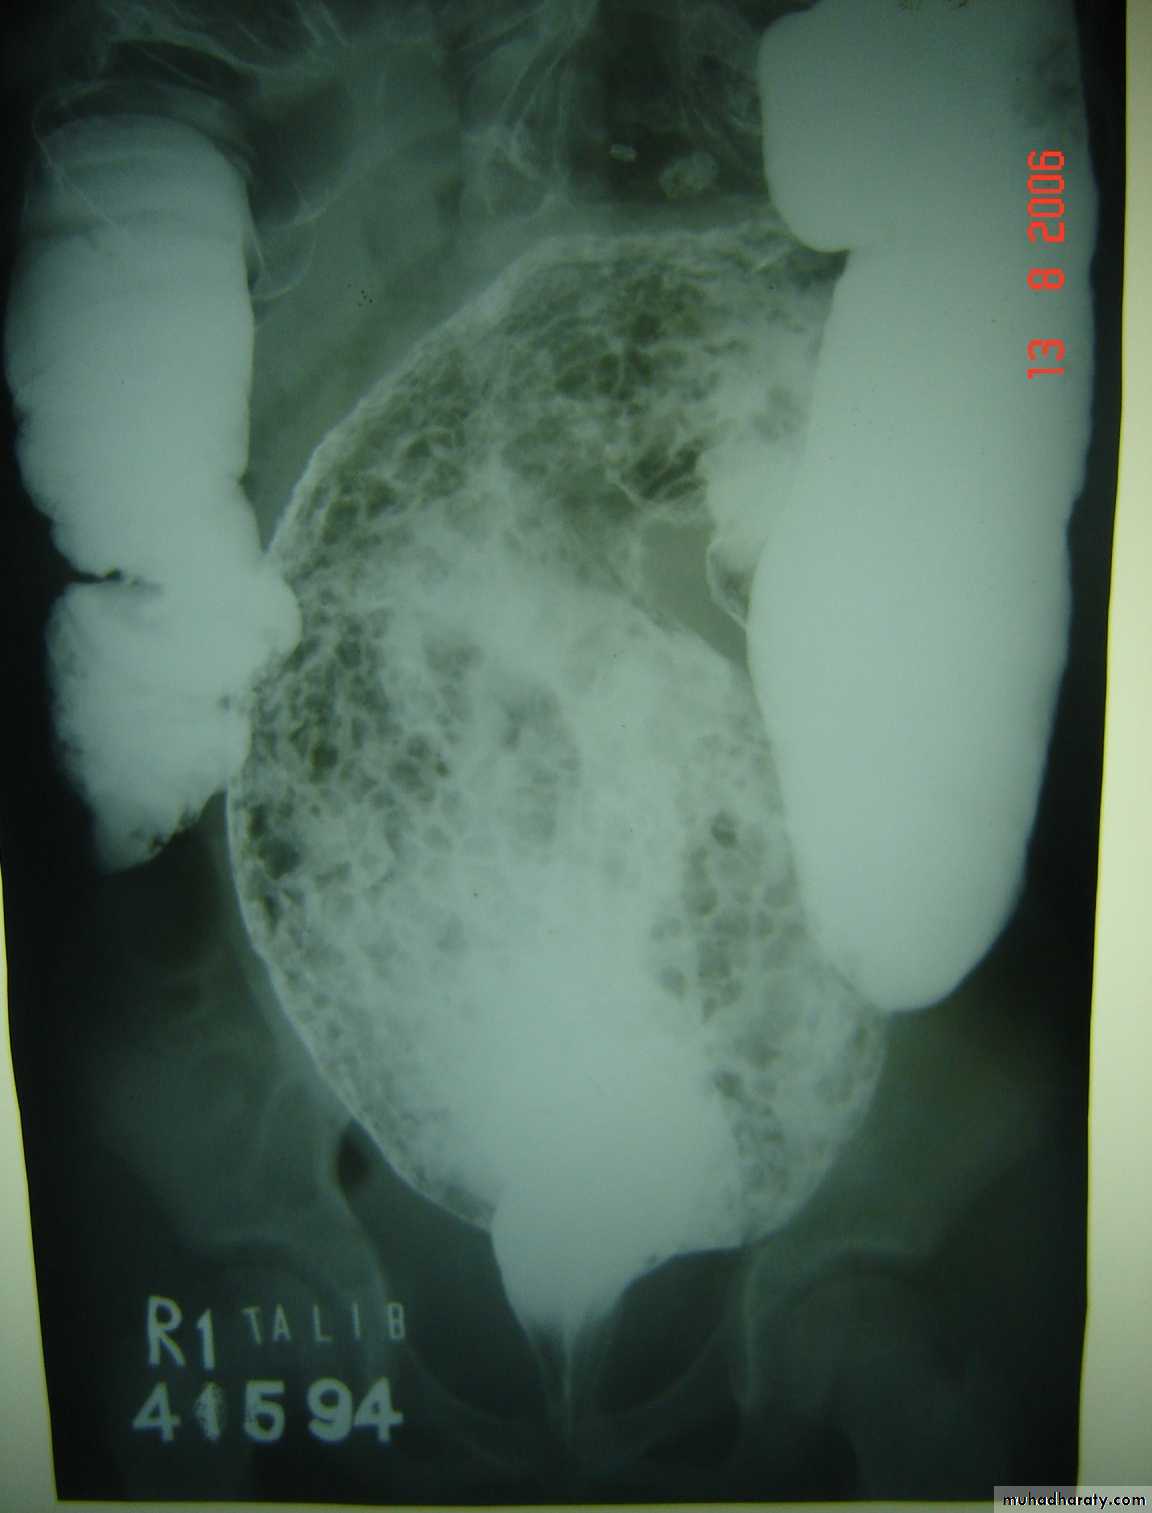

Hirschprungs disease

Description:

• Two years old child• Fist photo: Ba-enema test show dilatation of the sigmoid and narrowing of

recto-sigmoid junction and filled with material.

• The cause is problem in the ganglia